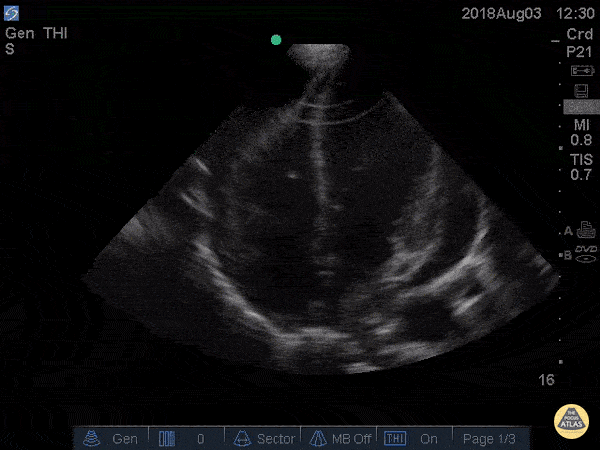

Pericardial Disease - Cardiac Tamponade Apical Four

41 yo M with history of stage 4 lung cancer presents with AMS and dyspnea, normotensive and tachycardic to 140s. Parasternal long view showed moderate pericardial effusion with RV collapse. With M mode we are able to see the RV wall collapse (top line) corresponds with the mitral valve opening i.e. it occurs during diastole. Even though the patient was normotensive he was taken to the OR for a pericardial window within the hour given this evidence of echocardiographic tamponade. Nathan Kabariti MS4, Dr. Charles Murchison, Dr. John Riggins, Dr. Donald Doukas - Kings County Emergency Medicine